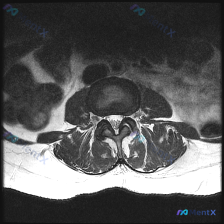

刚看到这份腰椎MRI轴位影像资料,整理了完整的读片和分析思路分享给大家。 一、基本影像信息 这是一张腰椎MRI的T2加权轴位图像,显示腰椎某节段横断面结构,结合形态判断大概率是L4/5或L5/S1这类腰椎好发受累节段,具体需要结合矢状位确认。 先把所有客观发现整理出来: 1. 椎体:前方椎体信号均匀...